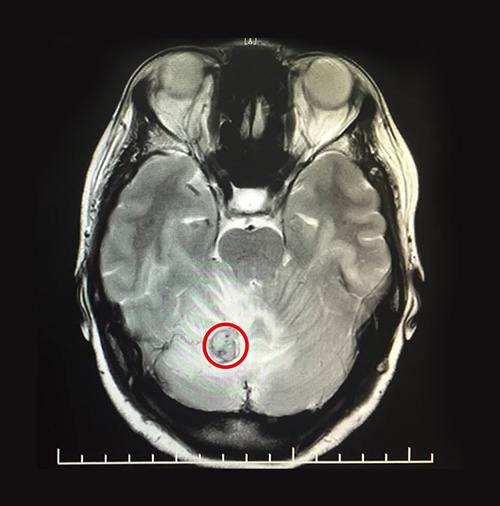

為了進一步明確病因,對患者又進行頭顱MRI平掃+增強+PWI+DWI,結(jié)果顯示:右側(cè)小腦半球見一異常信號灶,邊界清楚,T1WI為等高信號,T2WI等高信號,F(xiàn)LAIR呈略高信號,周圍見大片狀T1WI高水腫信號,DWI呈等低信號,病灶大小約15mm,增強掃描后可見強化。PWI示:右側(cè)小腦半球病灶區(qū)腦組織CBV、CBF明顯升高,MTT、TTP未見明顯異常。

▲MRI影像顯示,患者小腦有一個大小約15mmx15mm的腫瘤

最終孫阿姨被確診為小腦腫瘤,結(jié)合病史(她曾于2015年3月進行左腎切除手術)考慮轉(zhuǎn)移瘤。在診斷過程中,為了明確病因還進行了鑒別診斷,若是髓母細胞瘤,它多發(fā)于小腦蚓部,可伴小腦損害征,共濟失調(diào),病理檢查可鑒別。若是腦膜瘤,它的表現(xiàn)主要為顱內(nèi)壓增高及局灶性癥狀及體征,腦膜瘤多發(fā)于蛛網(wǎng)膜粒分布部位,結(jié)合CT可鑒別。

手術開始,在顯微鏡的助力下,醫(yī)術精湛的主任很快便精準的確定了患者的病灶區(qū),整個手術操作過程他都一絲不茍。術中,可見其紅色腫物,表面較光滑,血供豐富,充分切斷腫物周圍血供,最終完整切除了整個腫物,大小約15mmx15mmx15mm,歷經(jīng)3個小時,手術順利完成。